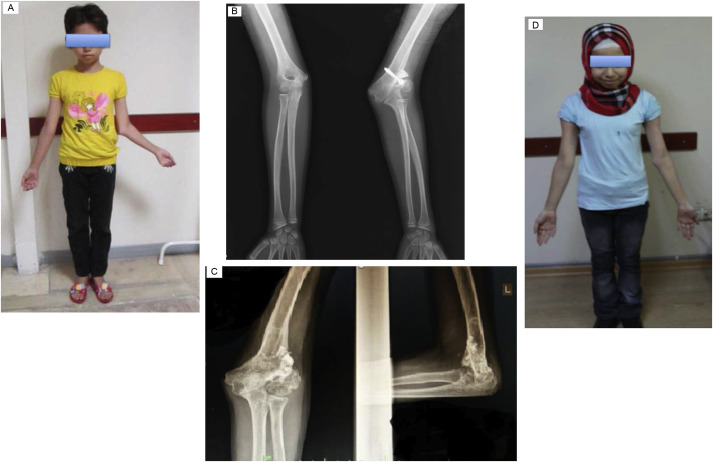

Fig. 3

Fig. 3.

Eleven-year-old girl with cubitus valgus deformity (patient #6). (a) Clinical appearance. (b) Anteroposterior radiography before correction. (c) Anteroposterior and lateral radiographs at last follow-up. (d) Clinical appearance at last follow-up.